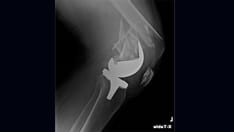

Avascular necrosis in the femoral head resulting from corticosteroid therapy.

Avascular necrosis of the shoulder showing subchondral radiolucent lines (crescent sign).